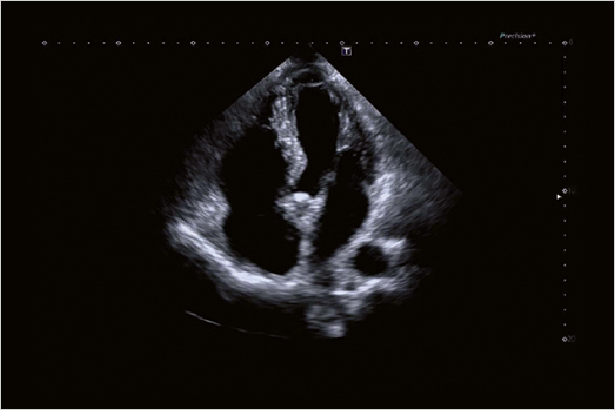

全新的Aplio i900帶給您晶透的圖像,多種深度都可以清晰呈現細節。

心臟實時3D成像讓Aplio i900可以對心臟的四個房室進行成像和定量。